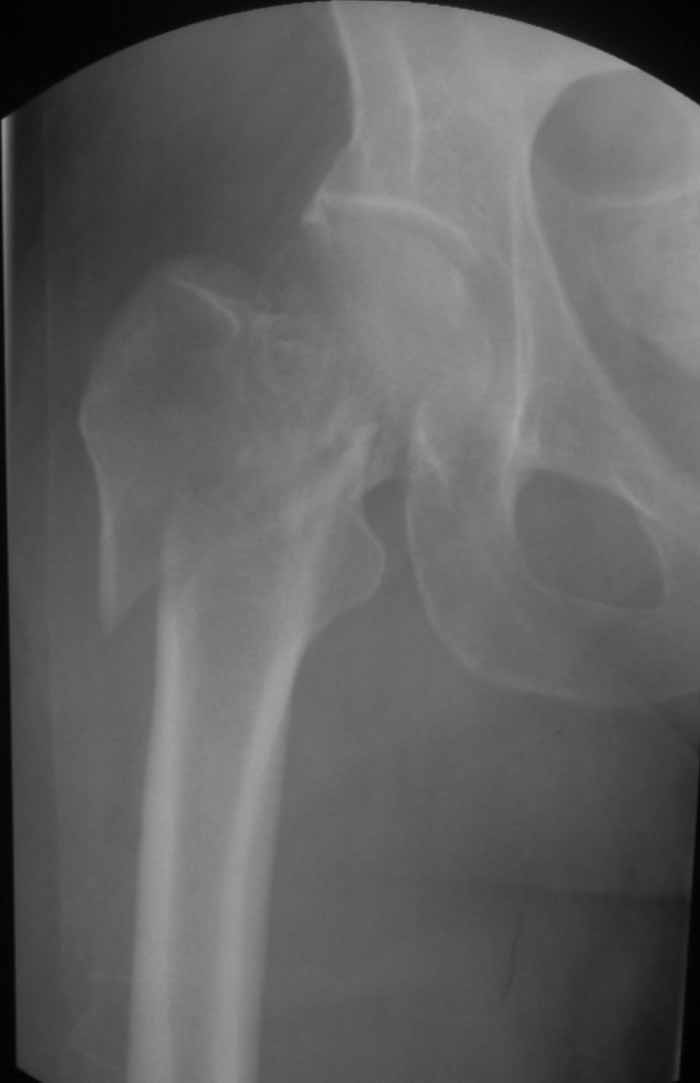

Пациентка 53 лет. ДТП 09.01.12: сочетанная травма: перелом 2-5 ребер справа, ушиб легких;

перелом обеих лонных костей без смещения; закрытый перелом проксимального конца правой

бедренной кости; открытый оскольчатый внутрисуставной перелом проксимальных концов

костей правой голени.

Бедро одномоментно делать не стал, не было уверенности в наличии перелома на уровне шейки. Во время операции смотрел тазобедренный сустав под ЭОПом,

головка неподвижна. После операции повторили КТ, стало очевидно, что имеется субкапитальный перелом. Что делать, остесинтез или протезирование? Если остеосинтез, то чем? Заранее благодарен за советы.